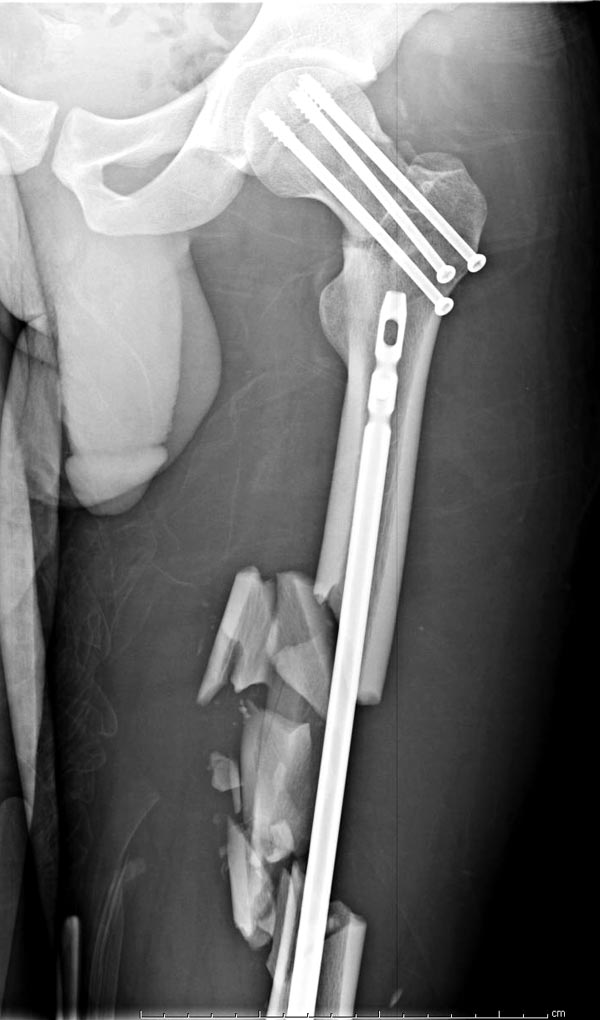

Здесь выставлен ренгенограммы больного, ему 21, травму получил в результате высокоскоростной погони на украденной машине, которая закончилась смертью трех остальных “боевых комрадов”. Начатую коллегой открытую операцию на шейке пришлось закончить мне, установкой винтов и ретроградной фиксацией бедра. Выписка в обычное сроки и наблюдался амбулаторно. Каждый раз напоминали о возможности осложнений ввиде несращения! По истечению 4 месяцев появились признаки варусной деформации. На СТ срезах несращение шейки и бедра. Риминг, замена на более толстый гвоздь и вальгусная остеотомия.

Сразу скажу, что пациент вчера (8.04) прооперирован - артротомия, остеосинтез мыщелков большеберцовой кости канюлированными винтами, открытая репозиция отломков бедренной кости, ретроградный БИОС, остеосинтез надколенника (центральных его отломков) спицами с проволочной петлей. Двухкратная попытка закрытой репозиции шейки на операционном столе после синтеза бедра - абсолютно неэффективна. Учитывая продолжительность и травматичность операции, шейка отложена на 2-й этап. Плечо наверное на 3-й (если вообще делать). Снимки постараюсь предоставить, но чуть позже.

И вопрос по представленному вами случаю - перелом шейки вроде как латеральный, почему остеосинтез винтами? Несращение и варус - закономерный результат?